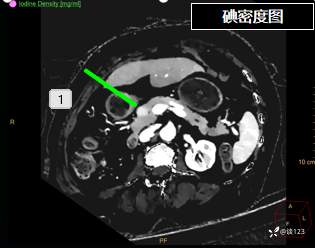

重新针对CT进行多参数后处理

这类病变不结合病史的情况,即使在CT静脉期有所异常也容易忽略;同时针对该类疾病使用胰腺增强方案应该更佳,好的诊断先决条件还是技术,技术不够CT新技术来凑。